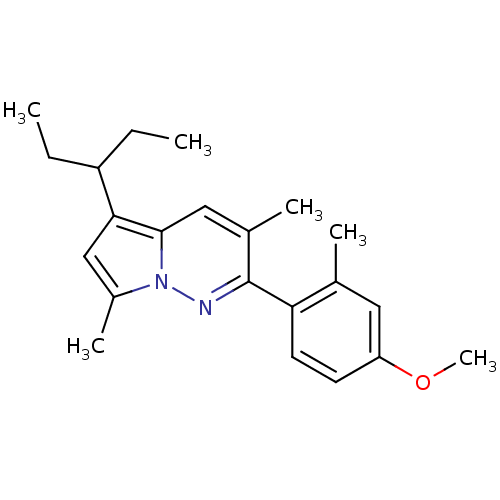

TargetCorticotropin-releasing factor receptor 1(Homo sapiens (Human))

Dupont Pharmaceuticals

Curated by ChEMBL

Dupont Pharmaceuticals

Curated by ChEMBL

Affinity DataEC50: 0.700nMAssay Description:Antagonist activity at human CRF1 receptor expressed in CHO-K1 cells assessed as inhibition of CRF-induced cAMP accumulation after 15 mins by cAMP en...More data for this Ligand-Target Pair